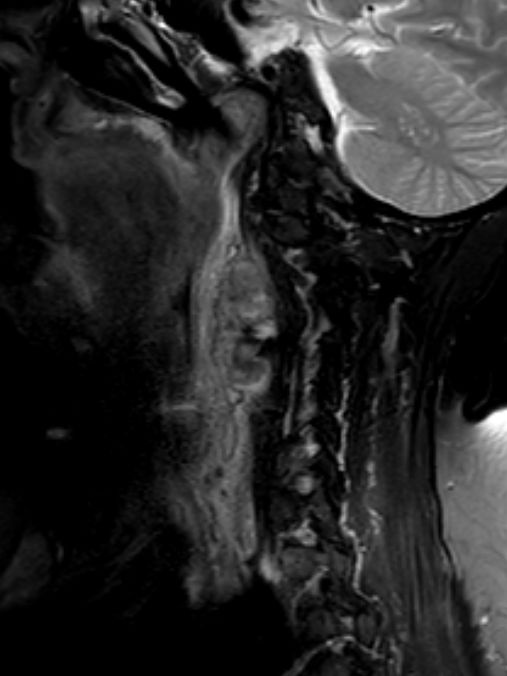

| Diagnostik | 88-jährige Frau mit einer progredientes

Dysphagie. Es besteht eine Raumforderung rechts retropharyngeal. Mukosa intakt.![]() |